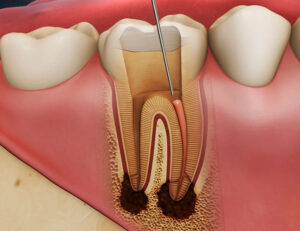

パーフォレーションが歯の寿命に与える深刻な影響

パーフォレーションが発生すると、その「穴」を通じて、歯の内部と外部(歯周組織や骨)が直接繋がってしまいます。

この状態を放置すると、以下のような深刻な問題が発生し、歯の寿命が著しく短くなります。

細菌の侵入と感染の拡大

穴が開いた部分から、口腔内の細菌が直接、歯の周囲の骨や歯茎に侵入し、根管内の感染とは別の新たな感染巣(病巣)を作ります。

特に、唾液が侵入することで感染は急速に進行します。

炎症と骨の吸収

穴の周囲で慢性的な炎症が起こり、歯を支える歯槽骨(しそうこつ)が溶け出します。

これにより歯がグラつき始め、歯周病のような状態に陥りやすくなります。

穿孔部位の出血と治癒の妨げ

パーフォレーションが起こると出血が生じ、その後の根管治療の視野を妨げます。

また、血が固まることで、根管内に正確な薬剤を詰める作業の妨げにもなり、治癒を困難にします。